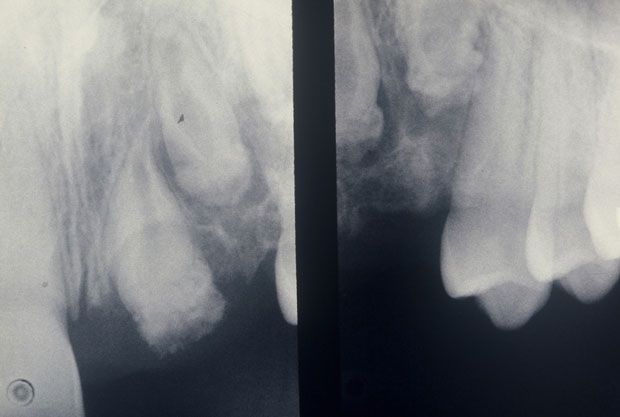

Radiographic imaging of the region (Figure 2) revealed malformed and impacted teeth, presumably the maxillary central, lateral incisor, and cuspid. The pulp chambers were large and root canals wide. The root portion of the structures was shortened and poorly outlined. Hypoplastic dentin and thin poorly mineralized enamel were barely evident. Remnants of follicular tissue surrounded the teeth below the lateral incisor. The cuspid was radiolucent with a "moth eaten" appearance.

Figure 2.